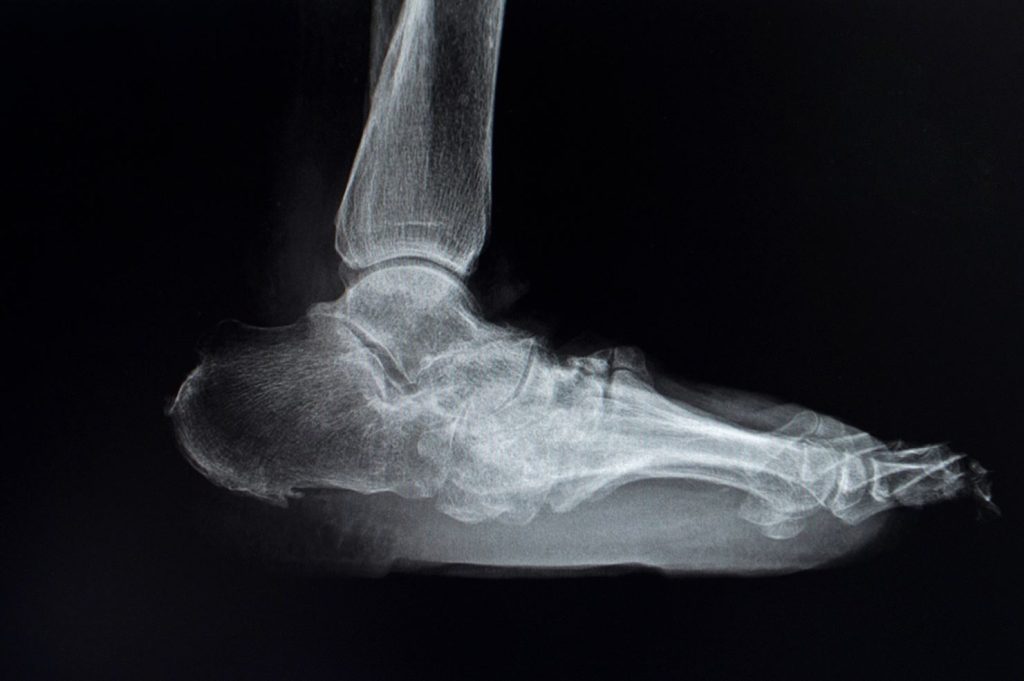

For many, the big toe joint is where gout shows up first (podagra). Yet it can also flare in the ankle or other parts of the foot, and the effect on mobility is immediate. When one side hurts, you can still limp and protect it, but when both feet are involved at the same time, there is no “good” side to rely on, and this makes a short trip to the bathroom an ordeal.

Gout symptoms often come on suddenly and escalate fast. It can start as a warm, throbbing sensation in a joint, then intensify into sharp pain that makes even small movements difficult. Although a flare can ease within a week, the joint often stays sensitive for longer, especially if you are still walking on it. Gout most commonly affects the big toe joint, but it can also affect the foot, ankle, and knee.

When gout strikes, it can turn a normal day into a struggle to walk comfortably, especially when the big toe, foot, or ankle is the joint taking the hit. At Straits Podiatry we first confirm whether your symptoms match the flare pattern of gout, then assess how the joint is coping with load through daily movement. Where useful, ultrasound imaging can also help us review the joint area more closely.